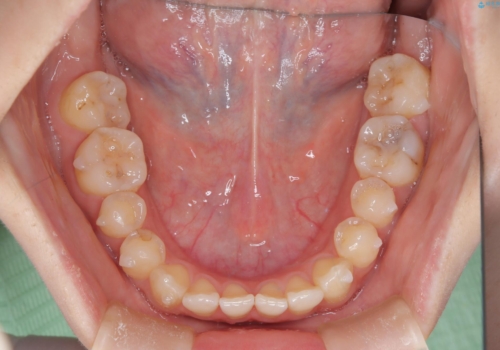

- 治療計画